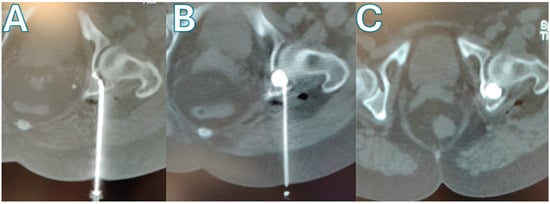

The management of severely comminuted acetabular posterior wall fractures in young, active patients presents a significant surgical challenge. When anatomical open reduction and internal fixation (ORIF) is not feasible, primary total hip arthroplasty (THA) is often considered but is a suboptimal solution due to concerns over long-term implant survivorship and the inevitability of revision surgery. This single-patient technical note presents a novel joint-preserving technique for managing unreconstructible acetabular posterior wall fractures using with cement-augmented screw fixation via the Kocher–Langenbeck approach. A 28-year-old male sustained a left posterior hip dislocation with a comminuted acetabular posterior wall fracture involving >30% of the articular surface, alongside a tibial shaft fracture, following a high-energy motorcycle collision. Intraoperative assessment confirmed the posterior wall was unreconstructible, with six non-viable osteochondral fragments. A joint-preserving salvage procedure was performed. After debridement, a stable metallic framework was created using three screws anchored in the posterior column. Polymethylmethacrylate (PMMA) bone cement was then applied over this framework in its doughy phase, meticulously contoured to reconstruct the articular surface. The hip was reduced, and the tibia was fixed with an intramedullary nail. The patient was mobilized with weight-bearing as tolerated on postoperative day 3. At the 21-month follow-up, the patient reported no pain during daily activities and only mild discomfort during deep squatting. Radiographic and CT evaluations demonstrated a stable hip joint, concentric reduction, well-maintained joint space, and no evidence of implant loosening or osteolysis. Level of Evidence: V (Technical Note/single-patient Case report). For unreconstructible, comminuted fractures of the non-weight-bearing portion of the acetabular posterior wall in young patients, cement-augmented screw fixation offers a viable joint-preserving alternative to primary THA. This technique provides immediate stability, facilitates early mobilization, and preserves bone stock. While long-term outcomes require further study, this case demonstrates excellent functional and radiographic results at 21 months, presenting a promising new option for managing these complex injuries. Full article

Show Figures

Figure 1